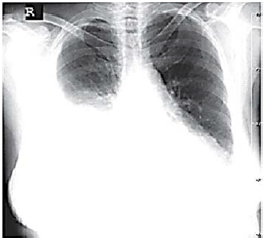

Uma paciente de 68 anos de idade, com queixa principal de falta de ar, tosse e dor torácica, relata ter iniciado, em fevereiro de 2019, quadro de tosse produtiva com escarro amarelado, febre, inapetência e dispneia aos grandes esforços. Houve piora evolutiva da tosse, além do aparecimento de dor torácica em topografia de base de hemitórax direito. A paciente é hipertensa e diabética e está em uso de enalapril, indapamida e metformina. Nega história de etilismo ou tabagismo. Ao exame físico, a paciente se encontrava hemodinamicamente estável, em regular estado geral, taquipneica (32 ipm), hipocorada (+/++++), normotensa e com oximetria periférica de 95% em ar ambiente. Na ausculta pulmonar, apresentou crepitações difusas em hemotórax direito. O aparelho de raio X estava quebrado. O hemograma evidenciou: leucócitos 14.500/mm3, com 3% de bastões; 30,4% de hematócrito; plaquetas 320.000/mm3; ureia 22 mg/dL; creatinina 0,5 mg/dL; glicemia 250 mg/dL; sódio 140 mEq/L; e potássio 4,5 mEq/L. Foram prescritos para uso domiciliar amoxicilina e clavulanato 500/125 mg, de oito em oito horas, por catorze dias e a paciente foi orientada a retornar em 72 h se não houvesse melhora dos sintomas.